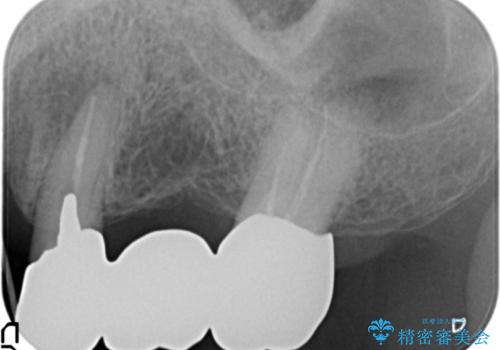

- 左上の歯ぐきが腫れていることを主訴に来院された患者様です。

精査したところ、歯ぐきが腫れている左上の小臼歯(左上4)は保存不可能な状態でした。

保存不可能な歯(左上4)を抜去後、ブリッジによる補綴治療を行いました。